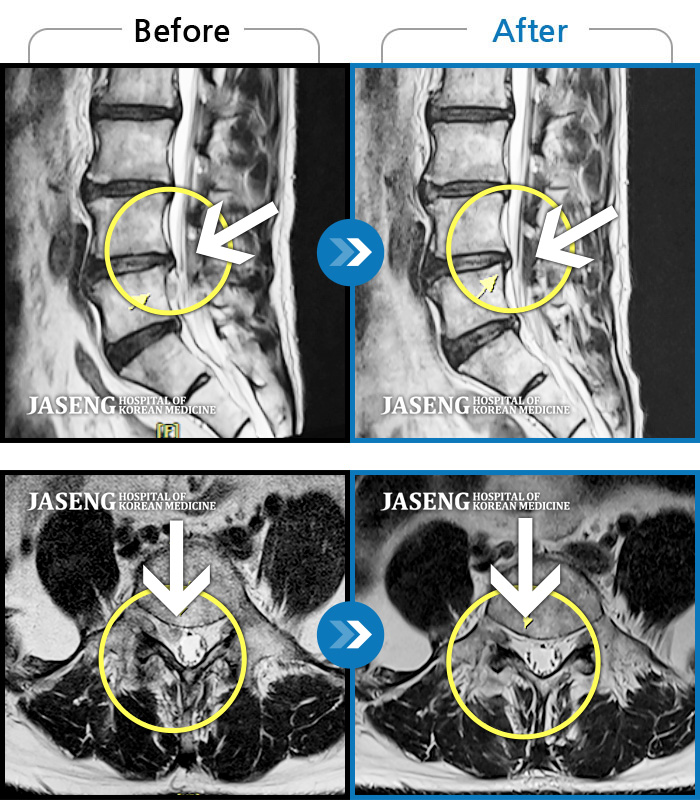

허리디스크

광주 · 김동은 원장

서 있거나 움직일 때 좌측 골반통증 및 좌측 하지 방사통과 발바닥 저림

촬영시기

2017.02.18 ~ 2017.09.13

2017.09.21

조회수 1,756